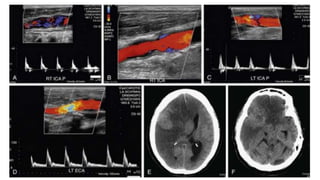

• #43 Aortic stenosis. Note tardus parvus waveform on spectral tracings of the right CCA (A), left CCA (B) decreased PSV and a delayed, more horizontal systolic upstroke with rounding or blunting of the systolic peak. , and left vertebral artery (C). The delay in systolic acceleration is even more pronounced in the right (D) and left (E) ICAs. This 79-year-old woman has severe aortic stenosis with a mean aortic valve gradient of 58 mm Hg and valve area of 0.73 cm.

• #51  Increased intracranial pressure. A, Spectral tracing of the right ICA from a 75-year-old woman with a large right hemispheric stroke reveals a knocking waveform with decreased PSV (24 cm/sec) and absent end-diastolic flow. B, Longitudinal color Doppler image demonstrates that the right ICA is widely patent. Magnetic resonance angiography (not shown) demonstrated occlusion of the right middle cerebral artery. Duplex Doppler interrogation reveals markedly reduced flow, both systolic and diastolic, in the left ICA (C), which was widely patent. Note that there is actually more diastolic flow in the left ECA (D) than in the ICA. These findings are due to increased intracranial pressure from the large right middle cerebral artery stroke. Axial CT images of the brain reveal both transtentorial (E) and uncal (F) herniation as well as the large middle cerebral artery stroke. Note midline shift and compression of the left lateral ventricle as well as obliteration of the right lateral ventricle (E).